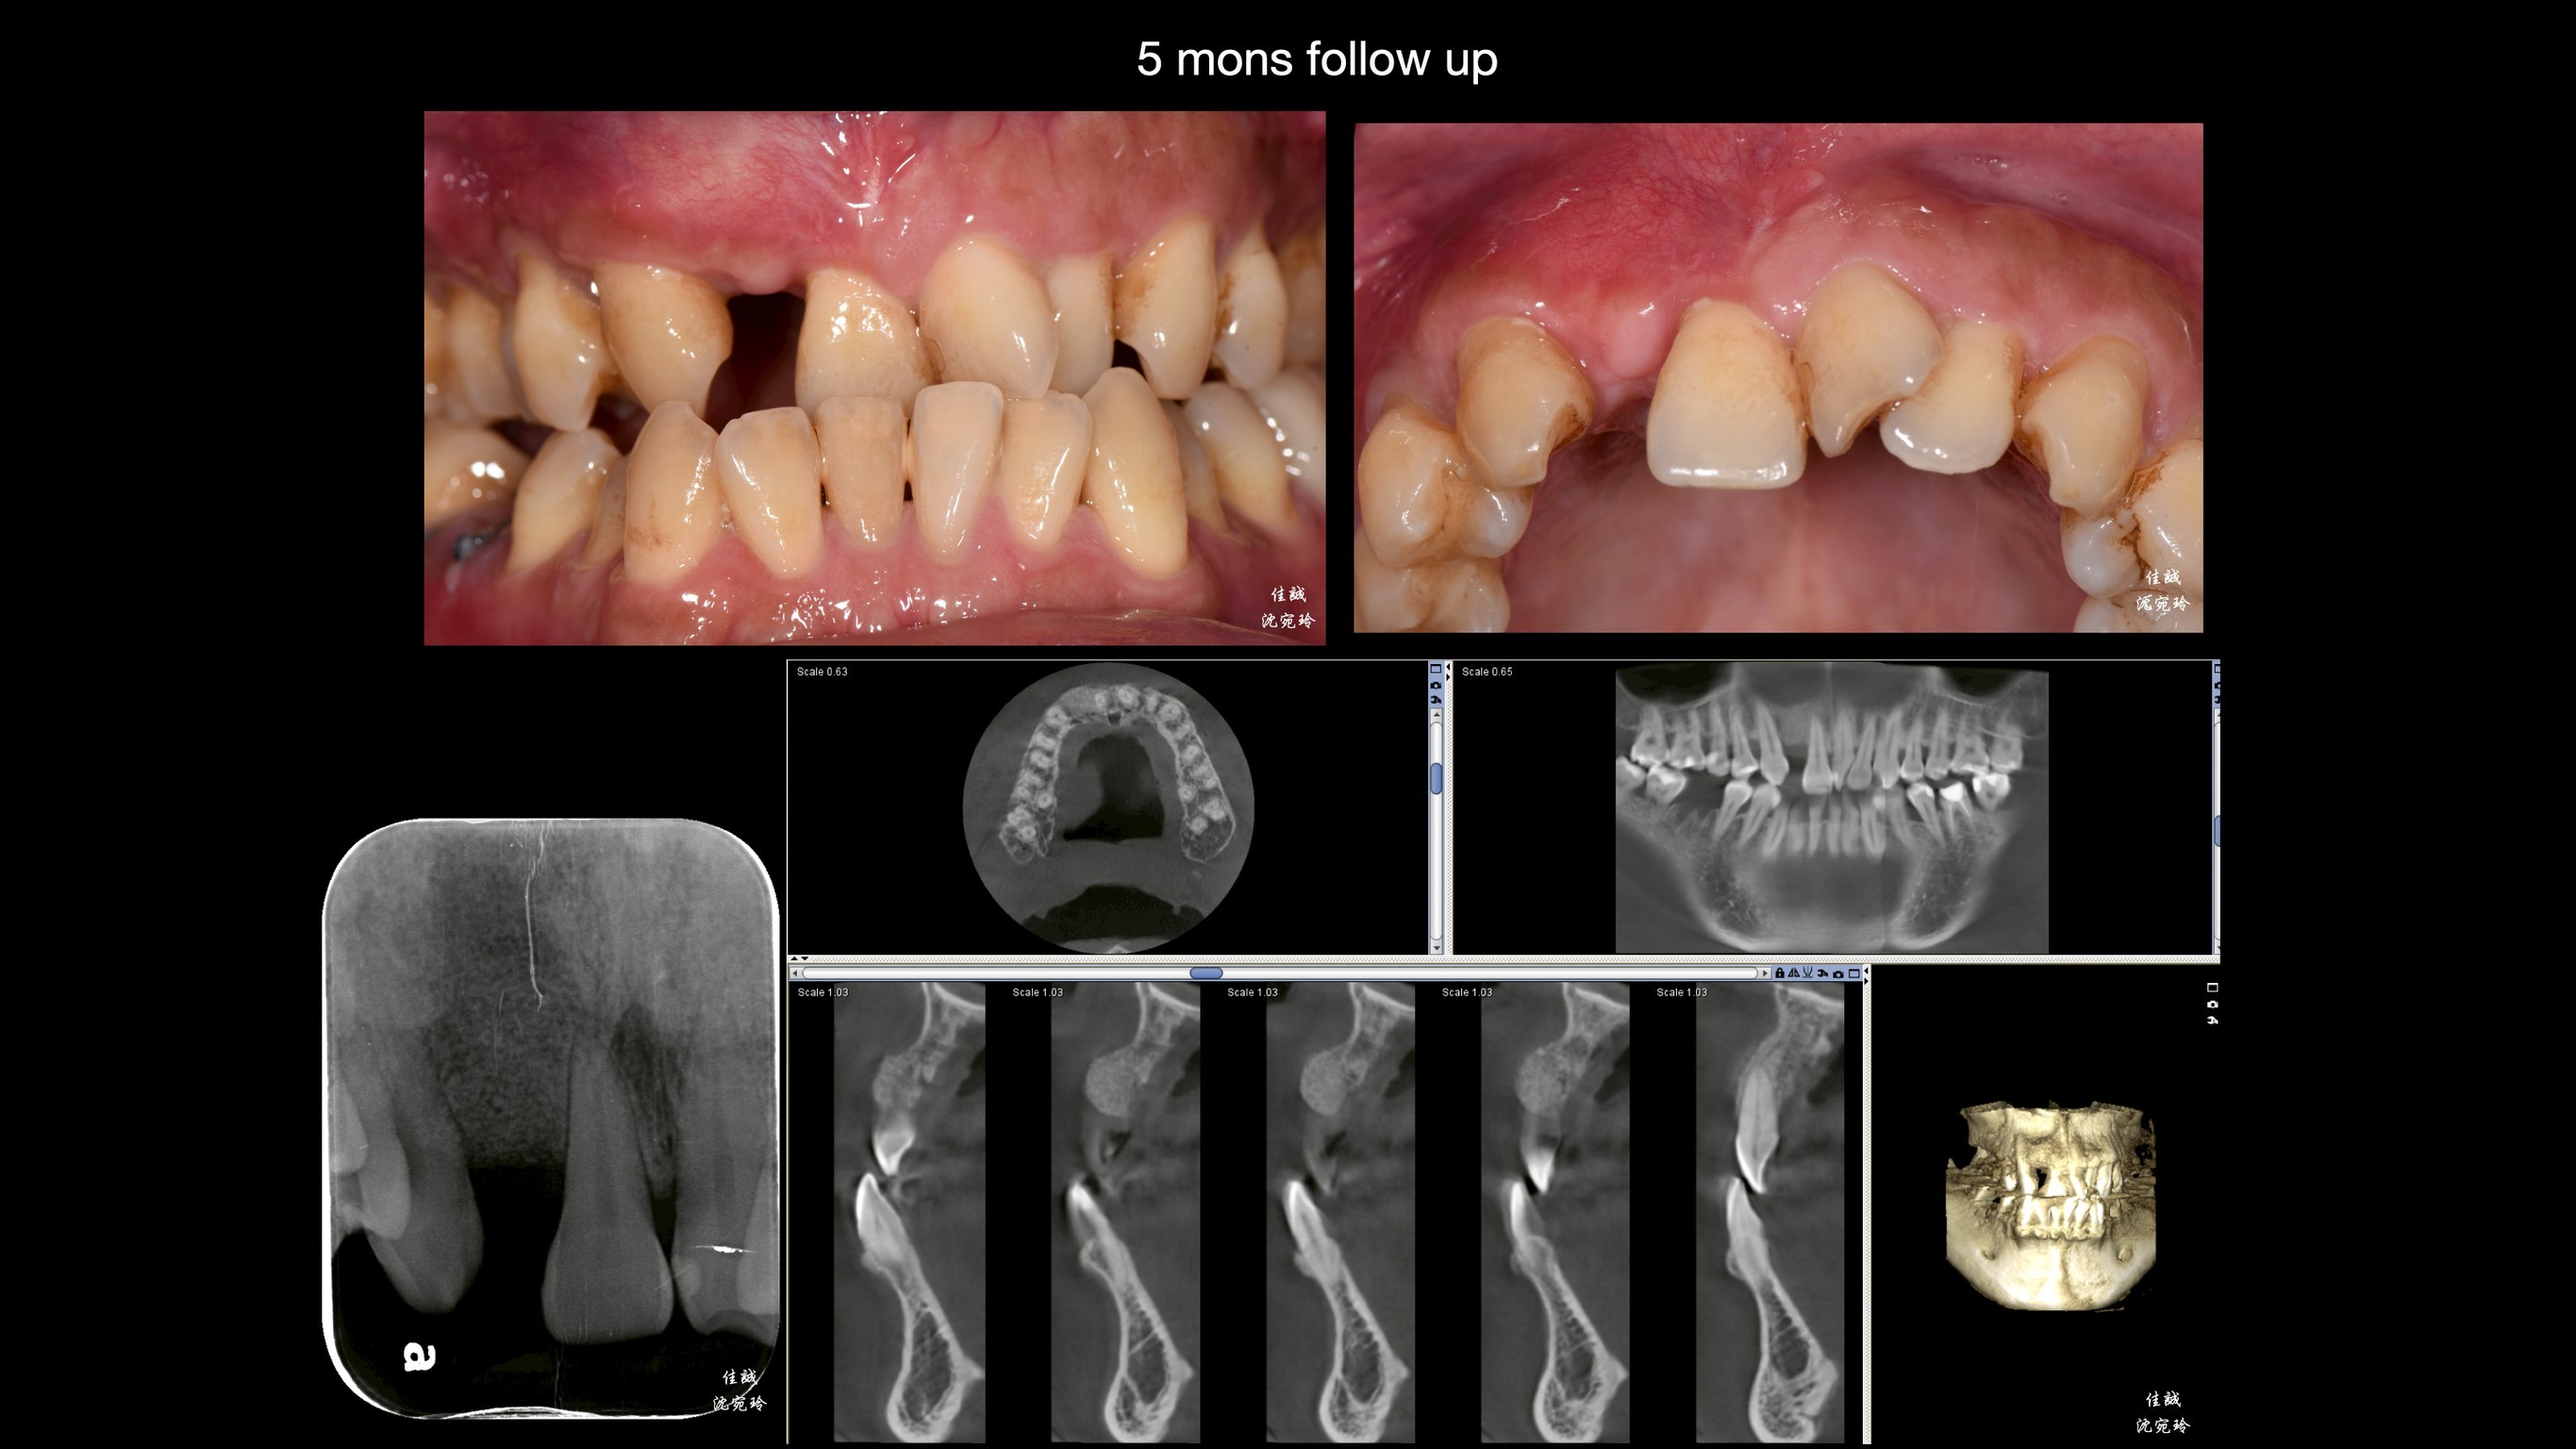

小插曲: 傷口術後1週回診追蹤,在嫩嫩的薄皮旁帶著明顯的瘀血腫脹,第2週回診看起來像第1週的癒合狀態,詢問之下才知道,患者術後2-3天開始做規律重訓,不過還好傷口沒打開,最後我們延後一週拆線,傷口也癒合良好。以往術後須知,我們只說「不做劇烈運動」,現在要多加個「不做重訓」了唷。

幾個月後,也仰賴病患體氣血循好,成果還不錯唷。